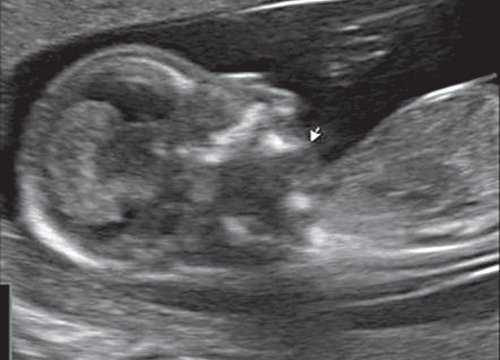

Пренатальный диагноз можно поставить с 24 недели, причём в 61,5% беременностей наблюдалось многоводие. На УЗИ выявляется анэхогенный double-buble 3 следствие расширение кишки и желудка.

Революцией в пренатальной ультразвуковой диагностике явилось появление объемной эхографии, которая, обладая такими качествами, как неинвазивность, безопасность и возможность многократного применения у одной пациентки, имеет высокую информативность в исследовании анатомии плода и изучении его фенотипа. При применении различных режимов объемной эхографии абсолютно очевидно их преимущество по сравнению с обычным сканированием. Детально можно изучить лицо плода (рис. 1-4) в различные сроки беременности, начиная со сроков первого пренатального скрининга в 11-14 нед, конечности плода, причем не только их наличие и положение (рис. 5, 6), но и состояние и количество пальцев (рис. 7-9) как на руках, так и на ногах. Также можно изучить позвонки плода (рис. 10), состояние твердого нёба (рис. 11, 12), строение наружного уха (ушной раковины) (рис. 13), состояние основных швов черепа и родничков, исключая их преждевременное закрытие при кранисиностозах (рис. 14, 15).